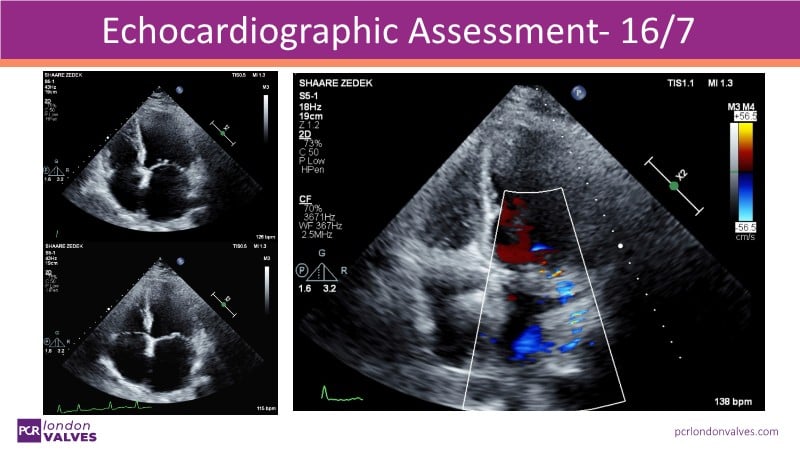

This LIVE case symposium brings mitral regurgitation guidelines into real clinical practice. Through step-by-step patient demonstrations and insightful discussion, the session explores how recommendations guide decision-making in ventricular and atrial secondary MR, how the heart team tailors therapy to individual anatomy and comorbidities, and how device iterations and procedural workflow can influence outcomes.